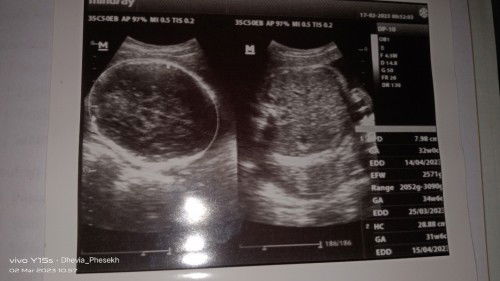

sekarang usia kehamilan bunda berapa? kalo dari hasil USG diatas dilihat dari BBJ itu usia 34w6d gak salah. untuk HPL gunakan sesuai HPHT atau USG TM1 bunda

kalau sekarang berdasarkan aplikasi usia kehamilan saya 33w2d Bun..baik bunda

yg EDD itu bun estimated delivery date